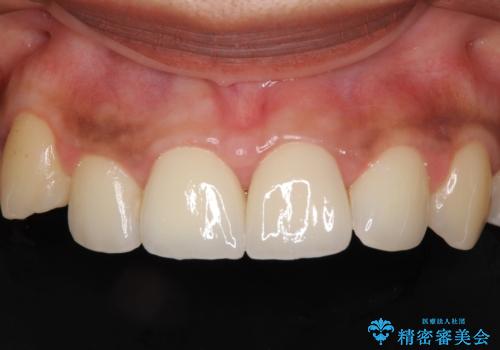

- 前歯の矮小歯と捻れや変色を気にして来院された患者様です。

結婚式が近いということもあり、前歯4本をオールセラミッククラウンにて補綴治療することとしました。

前歯の捻れは、オールセラミッククラウンよりも矯正治療による改善の方が、歯を削らなくて済むためお勧めとなります。

しかし、矮小歯の改善はオールセラミッククラウンでの補綴治療が必要であり、幅径のバランスを取る必要があるため、4前歯の補綴治療を選択しました。